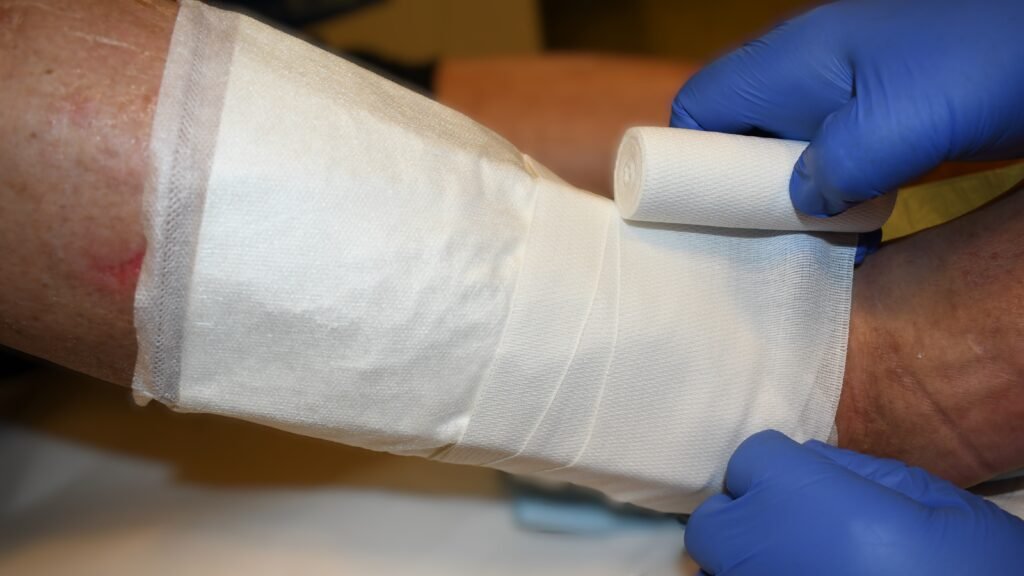

Fixierbinden

Zusätzliche – Fotos ![]() 3 Videos

3 Videos ![]() 1

1